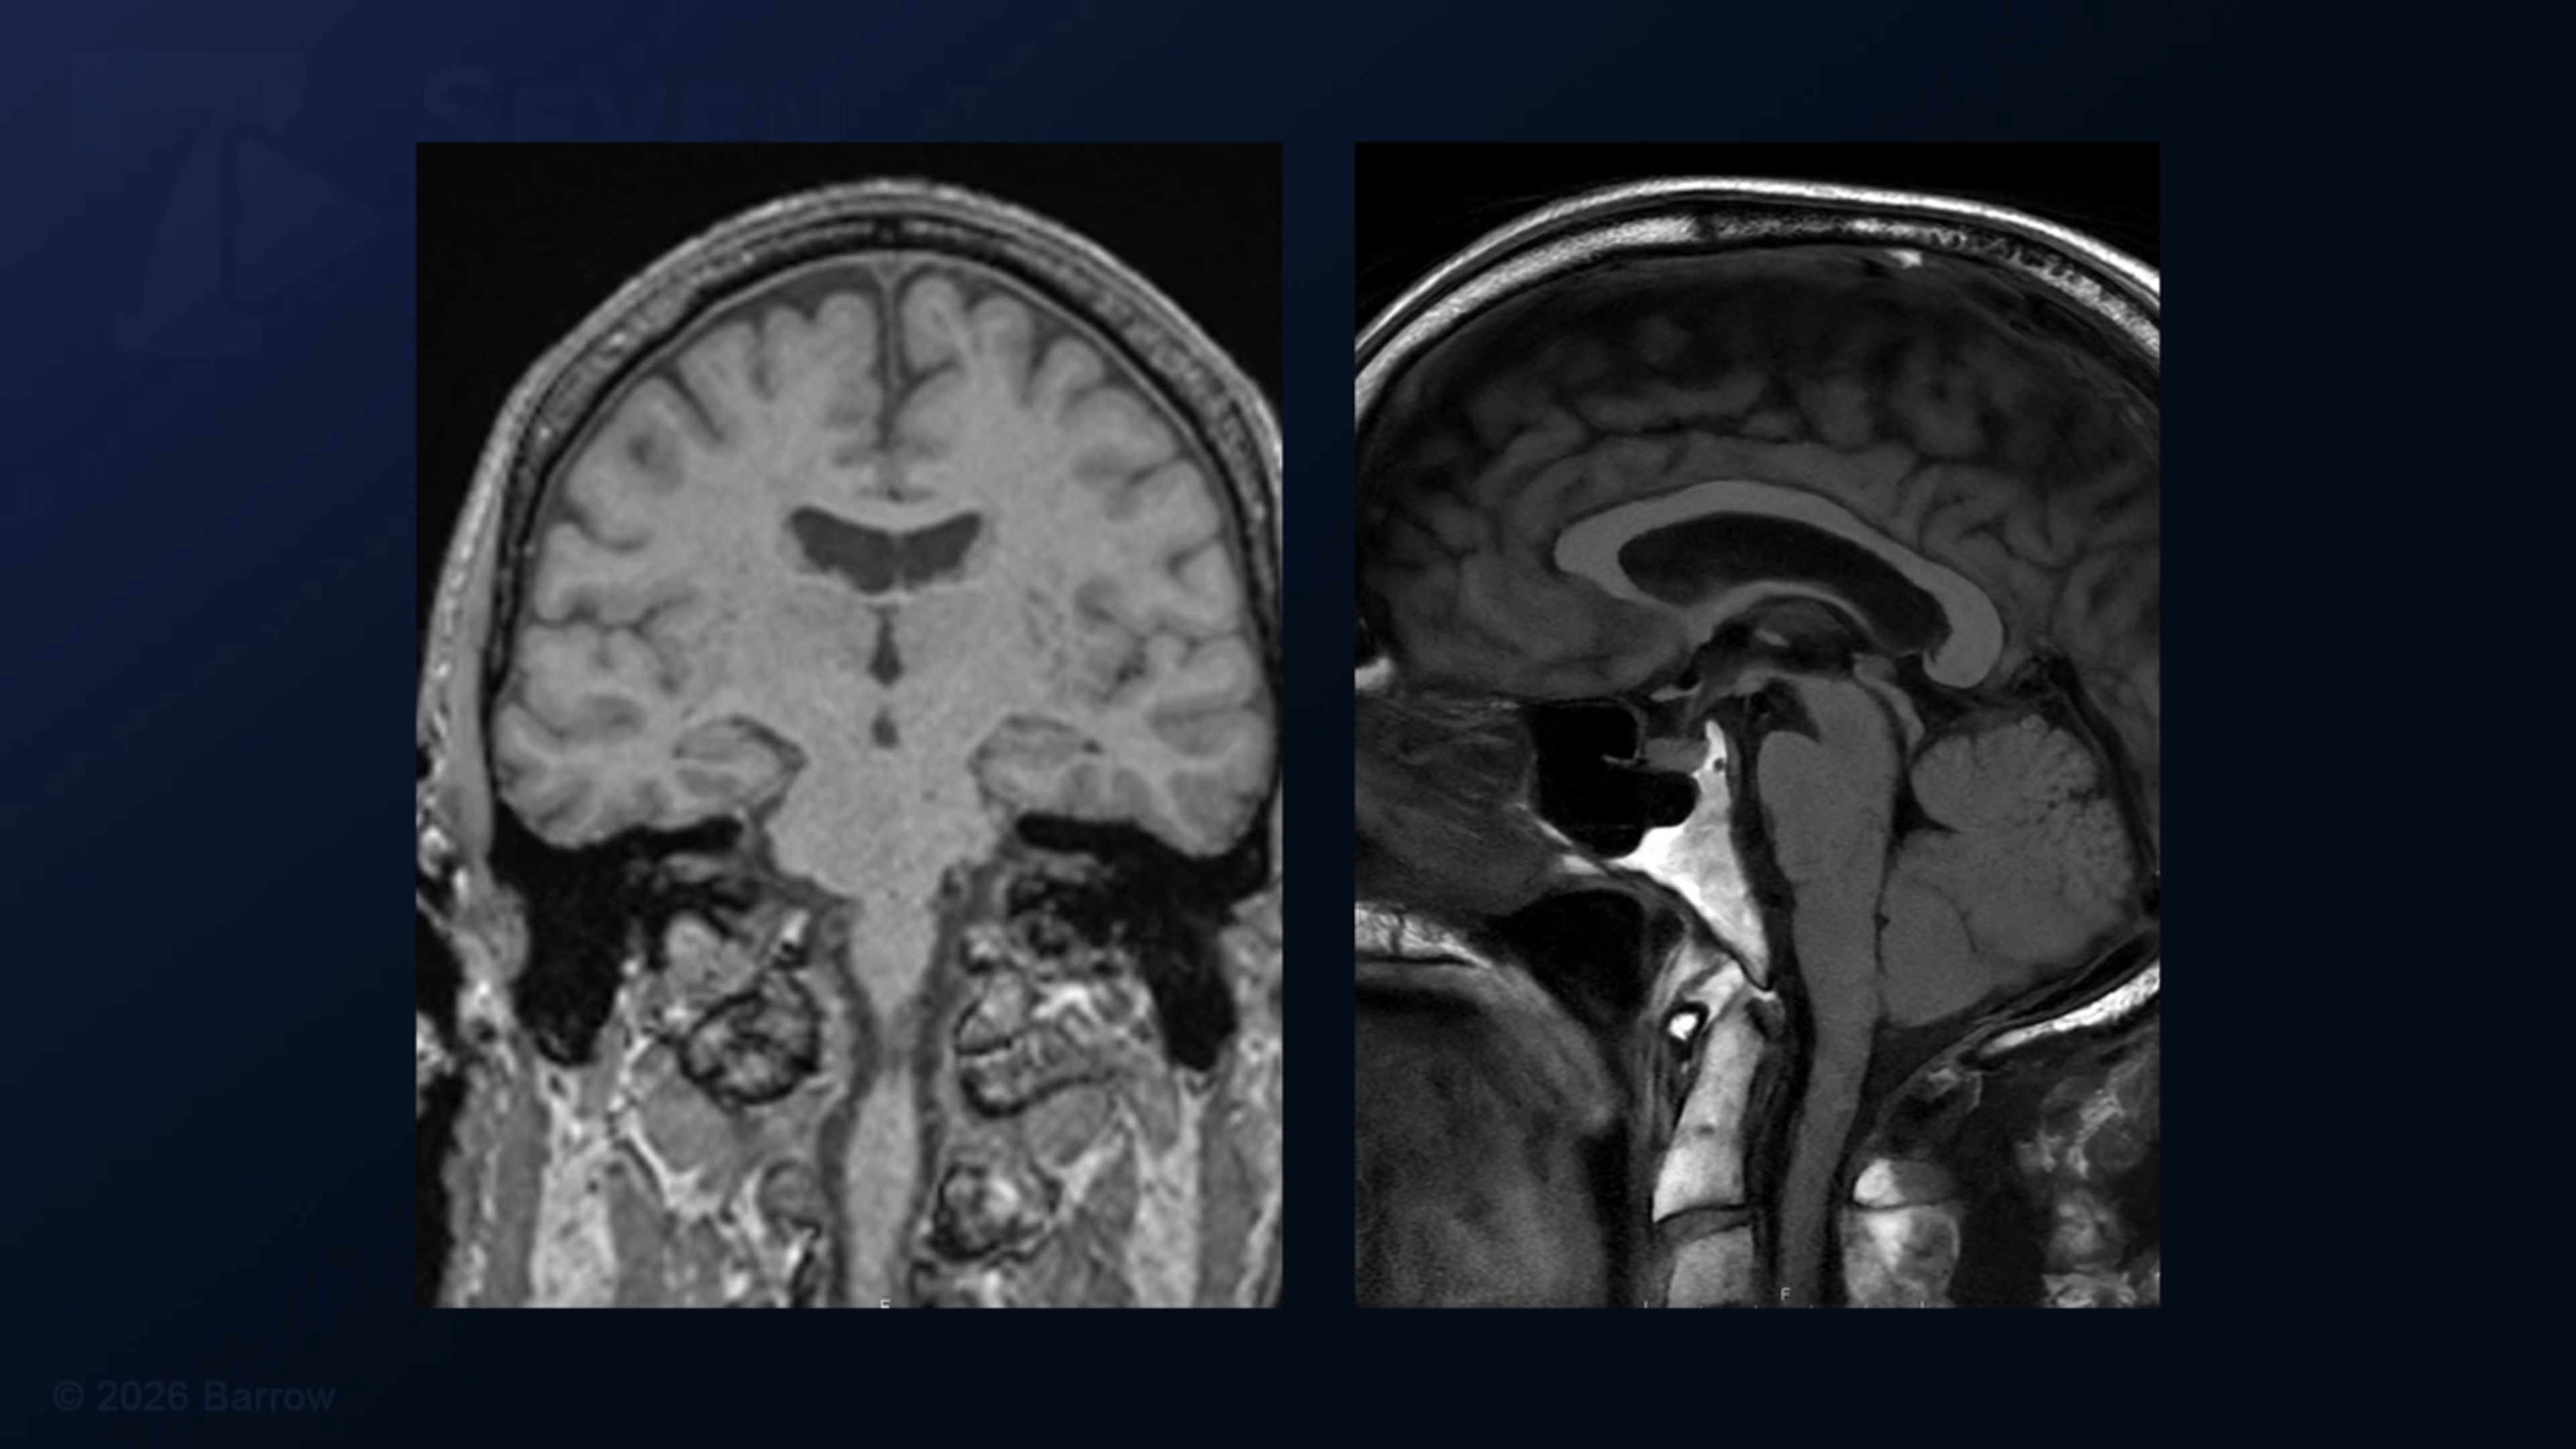

Episode 498 of Seven Series shows a management of a transected occipital sinus during far lateral craniotomy for a foramen magnum meningioma (FMM) resection.